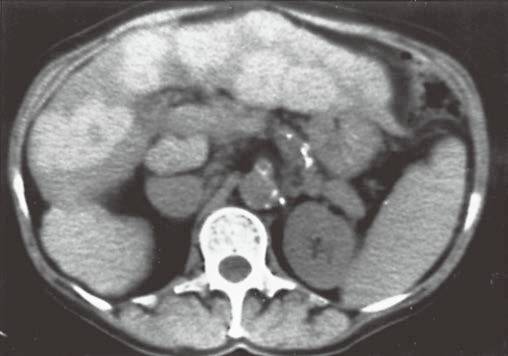

| 脂肪浸润(图1〜图 3) | 肝脏密度弥漫性减低。在肝脏脂肪变的低密度背景下,门静脉表现为高密度结构(平扫时正常门静脉呈低密度)。 | 由于三酰甘油过度沉积所致,见于肝硬化或其他肝脏疾病。正常肝脏平均CT值不低于脾脏,肝脏脂肪 浸润时CT密度较低。肝硬化引起脂肪浸润,伴有肝右叶萎缩,尾状叶体积增大。 |

图2肝硬化患者的肝内斑片状脂肪浸润